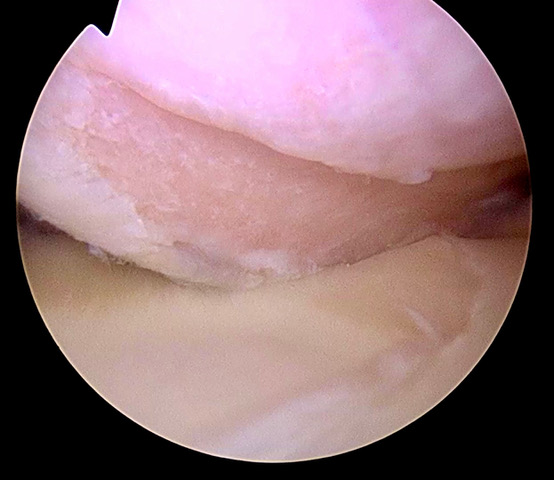

En la mayoría de los casos el diagnóstico se apoya en pruebas complementarias como la radiografía o la resonancia magnética. Uno de los objetivos principales de estas pruebas es determinar si sólo hay lesión del lábrum y los ligamentos del hombro (la conocida como “lesión de Bankart”), o si también se ha producido una pérdida de hueso del húmero o de la glenoides como consecuencia del impacto entre ambos en cada episodio de luxación. Conocer esto es muy importante para saber qué tipo de intervención quirúrgica hay que realizar. Si sólo hay lesión de Bankart, se puede realizar una reparación por vía artroscópica. Si hay pérdida de hueso, hay que suplementarte con un injerto. Tomar la decisión de realizar una u otra operación, así como ejecutarla, requiere de una amplia experiencia y conocimiento sobre la enfermedad.